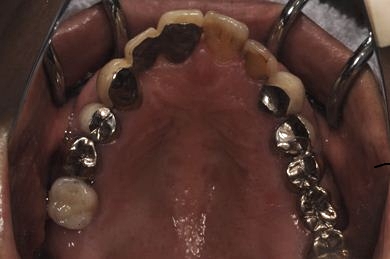

治療前

• 治療前